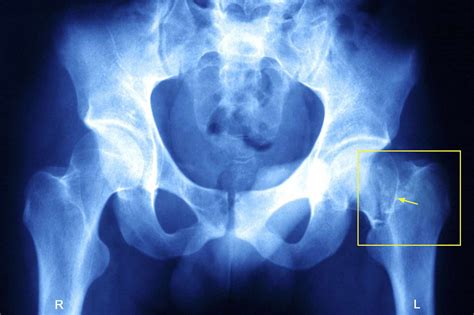

Illustration of a hairline crack in the hip bone

The hip joint is a ball-and-socket joint that bears a significant amount of the body’s weight. When we speak of a cracked bone in hip, we are usually referring to a stress fracture—a tiny fissure in the bone caused by repetitive force—or a hairline fracture resulting from a minor trauma. While these are not as catastrophic as complete hip fractures, they must be taken seriously to prevent them from progressing into more severe injuries.

If you suspect you have a cracked bone in hip, seeking prompt medical attention is non-negotiable. A doctor will typically perform a physical examination, checking for point tenderness and range of motion. Because hairline fractures are notoriously difficult to see on standard X-rays, especially in the early stages, your physician may order advanced imaging: